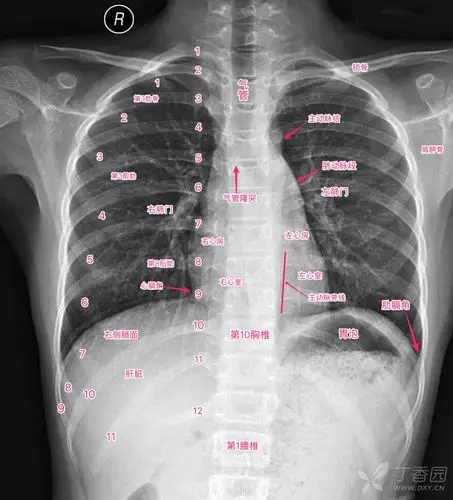

丁香园